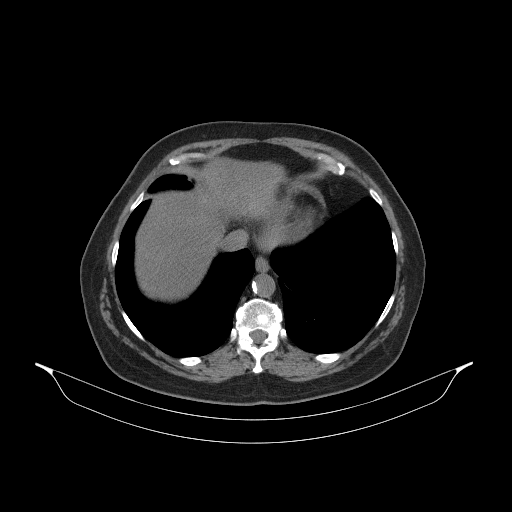

Generated VENOUS CT scan (A→B translation)

Full window (WL 1023.5, WW 4095 β†’ Low βˆ’1024, High +3071)

Actual HU range: [-1024.0, 1197.0]